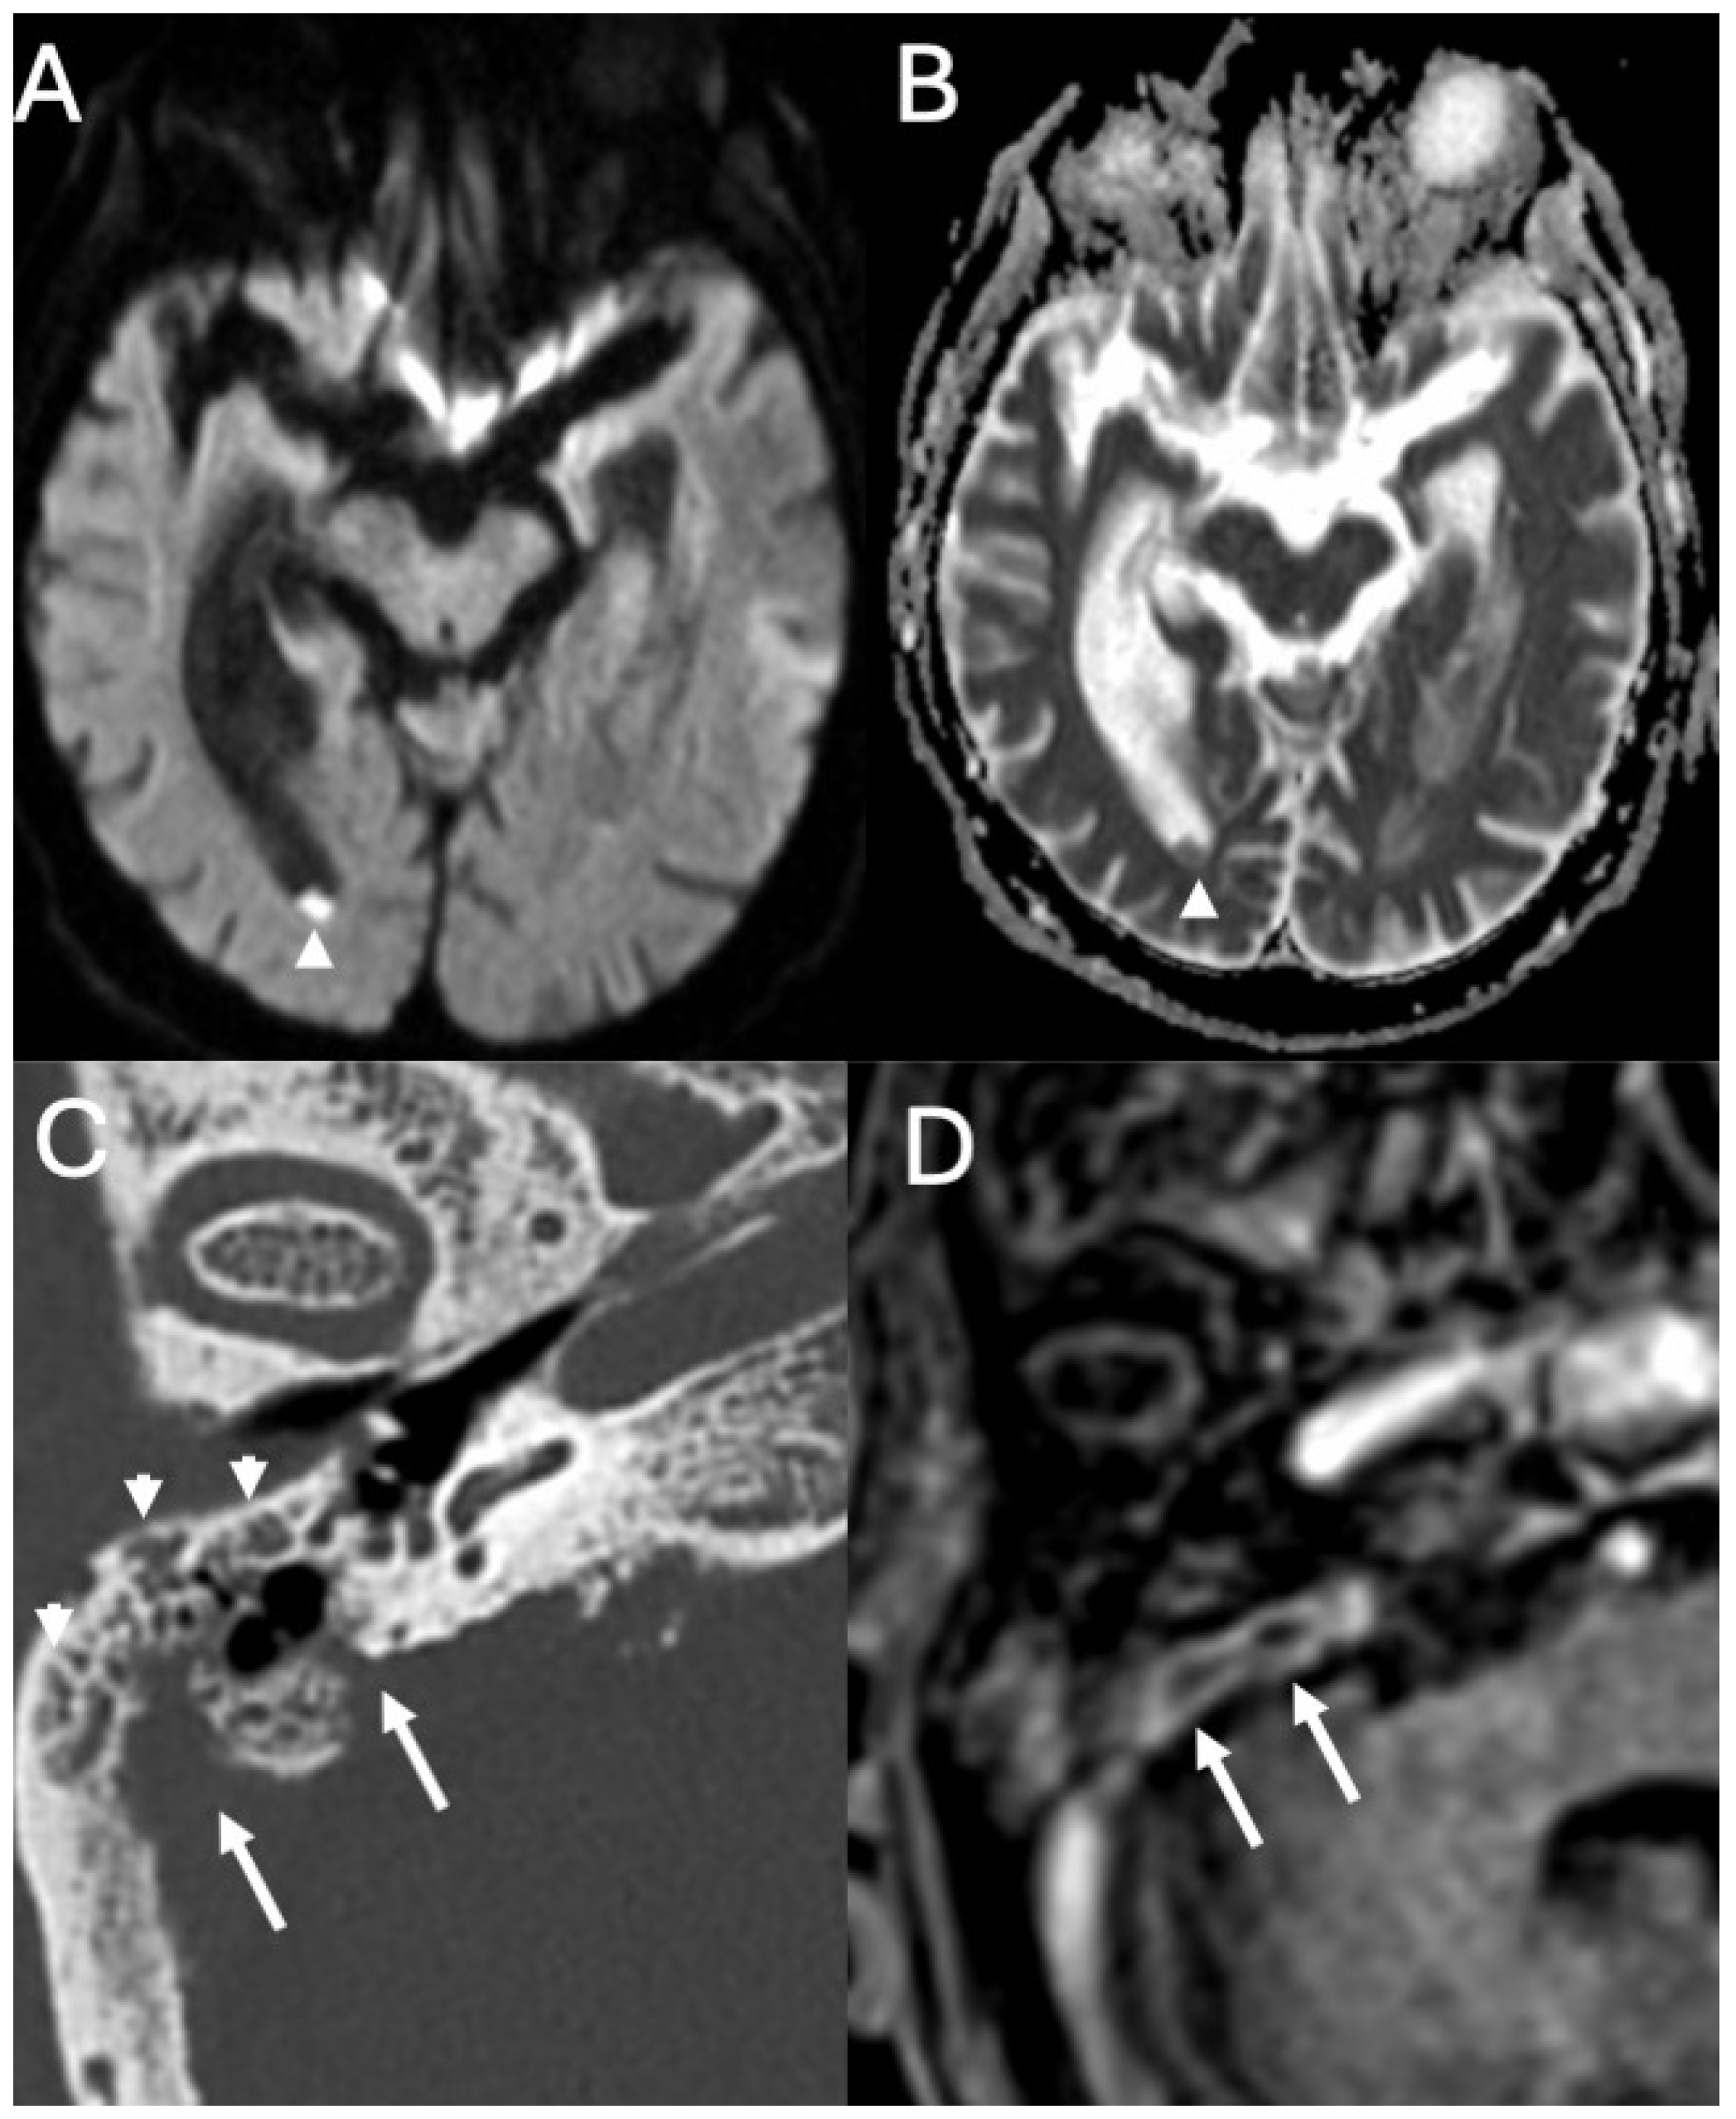

3.1. Otomastoiditis

3.1.1. Imaging

3.2. Bony Dehiscence

3.3. Cholesteatoma

3.3.1. Imaging

3.3.2. Complications